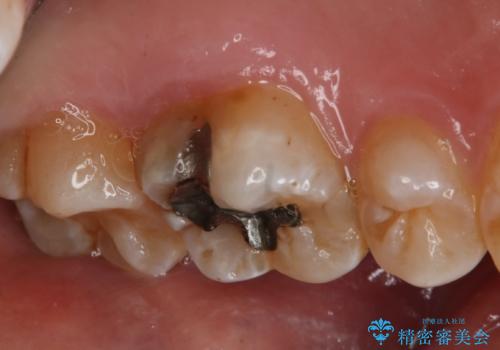

- 左上6番の銀歯のやり変えを希望し来院された患者様です。

切削量・形態を考慮し、セラミックインレーでの治療を計画しました。

銀歯直下のう蝕が深かったのでCRで裏層した上で形成、印象をしています。